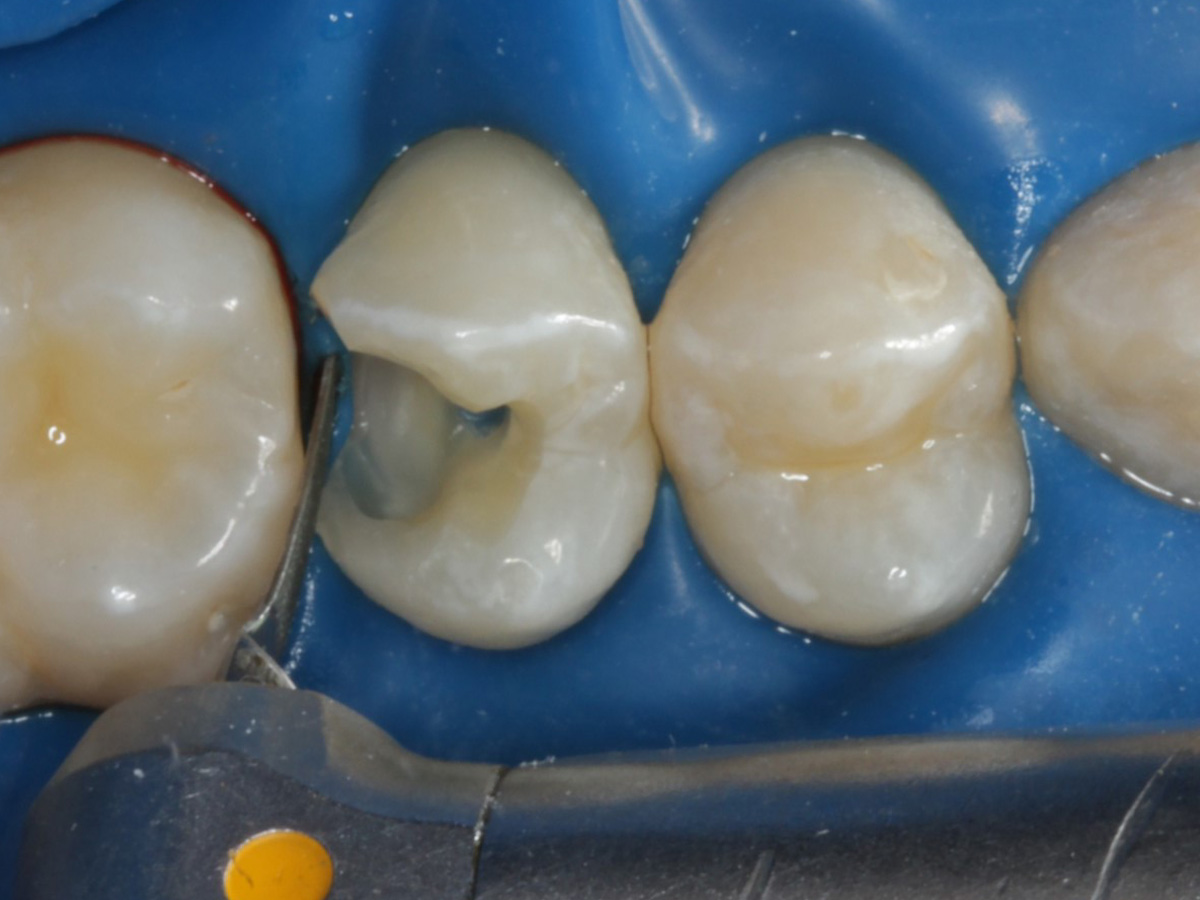

Abbildung 9

Nach Applikation der Matrize: Evolve Schwarz Prämolar- 7 mm; Schmelzätzung

Abbildung 10

Nach Spray und Trocknung der Kavität: perfekte Adaptation der Matrize insbesondere tief subgingival